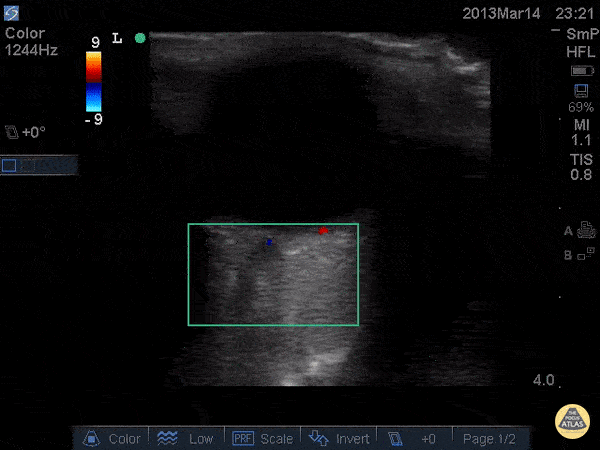

Only venous flow can be appreciated in this color flow image. The central retinal artery has been occluded. Dr. Joshua Schechter - SUNY Downstate/Kings County Emergency Medicine